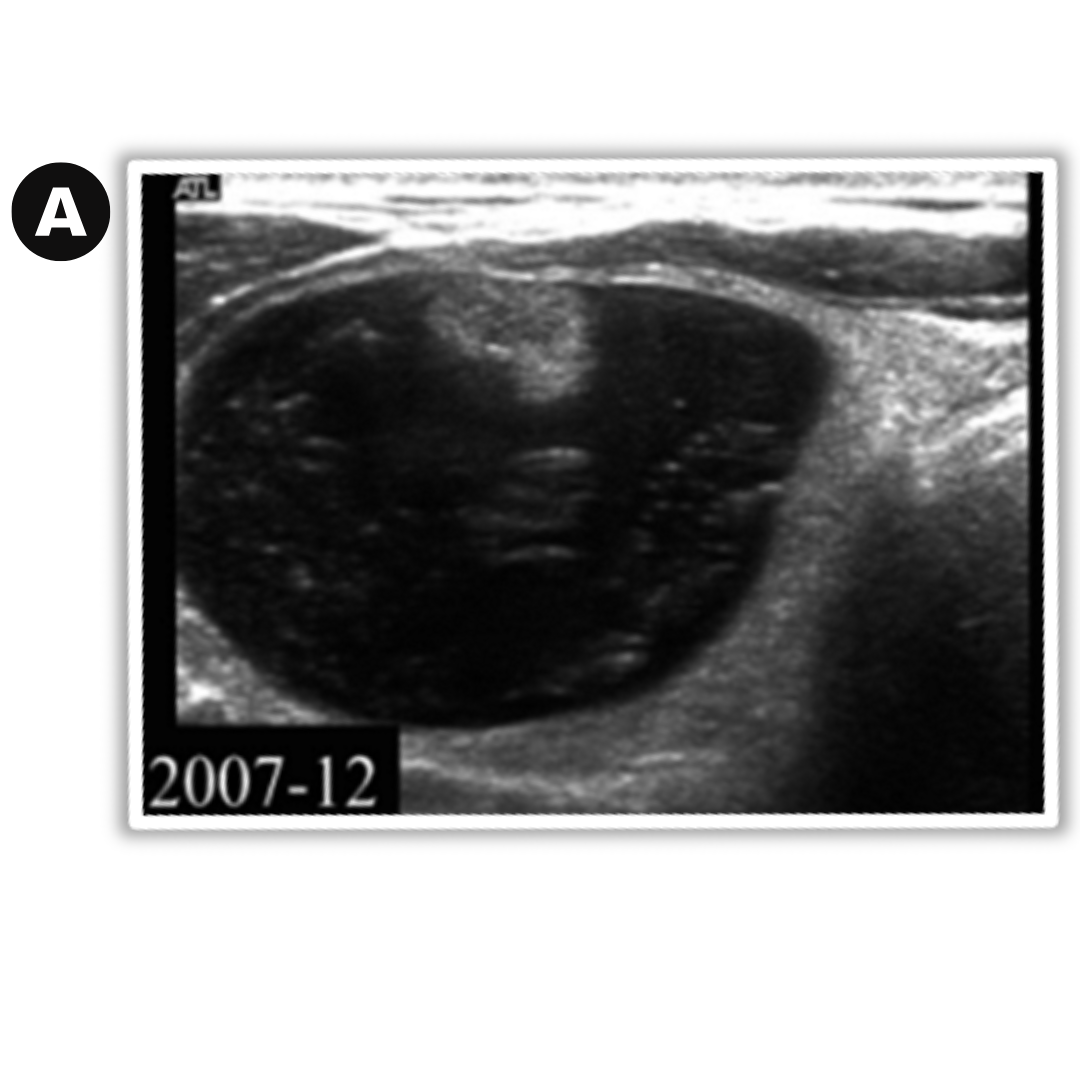

Caso 01: Nódulo en control a) diciembre 2007 nódulo coloideo predominantemente quístico b) diciembre 2010 nódulo en degeneración, muestra un nódulo sólido hipoecoico con focos ecogénicos.